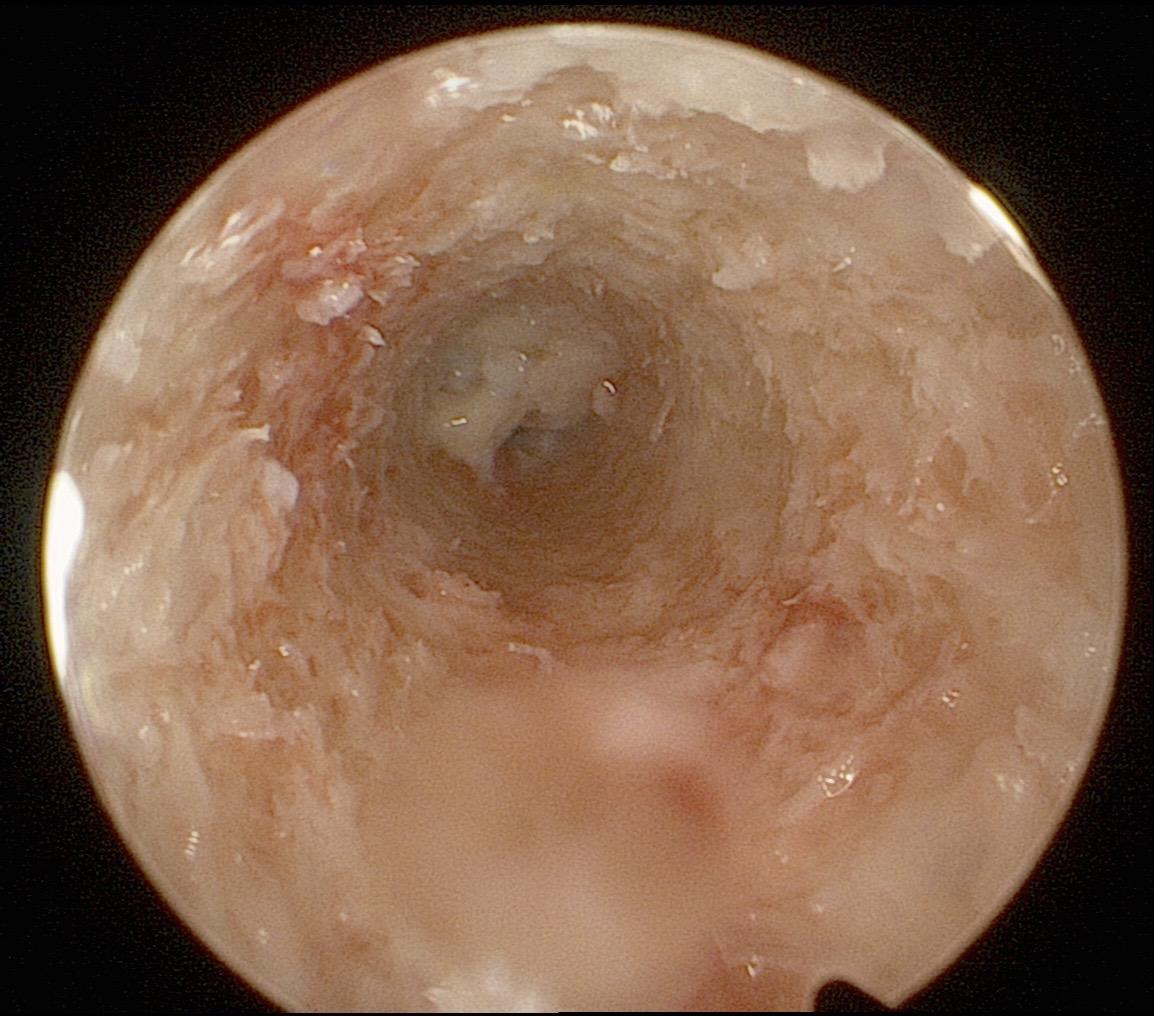

前交叉韧带重建。面对前交叉韧带的断裂,我们选择重建。希望这根强大的移植体,能为他撑起一片天,让他再次在运动场上放飞自我。前交叉韧带重建 前交叉